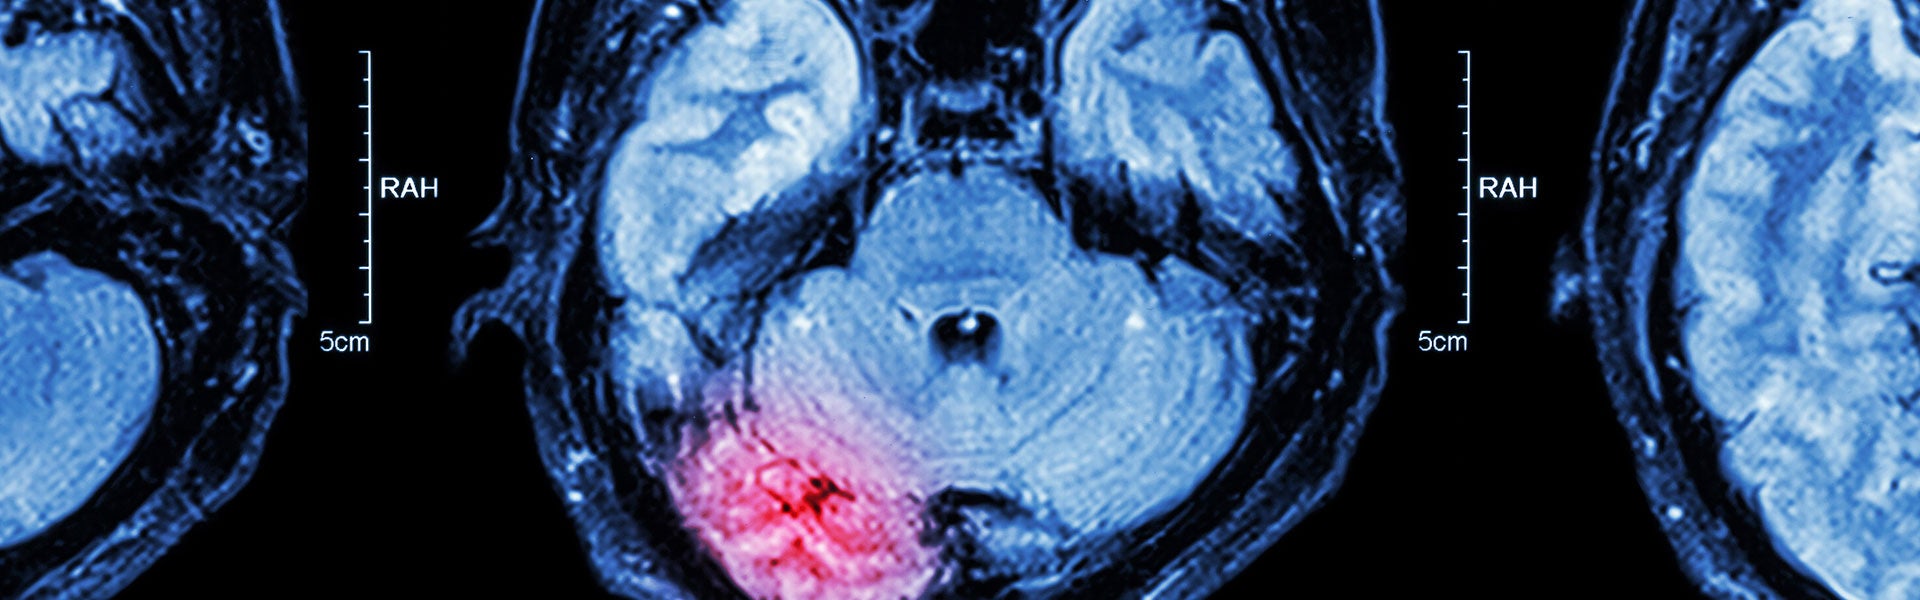

The brain is a marvelous creation, responsible for so many essential functions of the human body. Suffering a traumatic brain injury can therefore have disastrous consequences, leading to long-term and perhaps permanent health complications and disability. If the injury was caused by someone else’s negligence, the victim has the right to seek compensation.

The Centers for Disease Control defines a traumatic brain injury (TBI) as an injury that disrupts the normal function of the brain. It may be caused by a bump, blow, or jolt to the head, or a penetrating head injury (such as a gunshot wound). A TBI can generally be grouped into one of three categories: